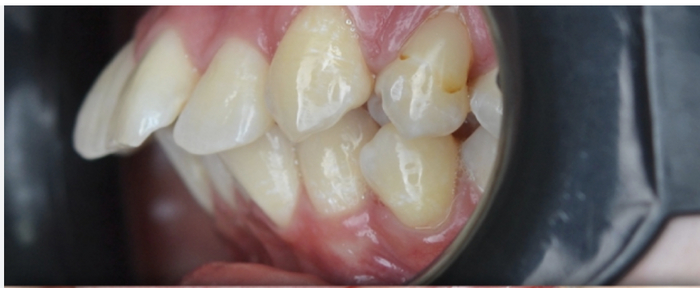

На данных двух фото моя "отдыхающая позиция" челюстей, в которой мне комфортно их держать. Даже с очень глубоким прикусом контур моей челюсти всё равно можно увидеть, из-за того что она в принципе у меня большая, больше чем у моего отца (возможно к этому как-то причастно то что я дышу через нос и держу язык в верхней половине рта т.е. возможно я неосознанно выполнял предписания той самой теории "мьюинга", хз правдива она или нет). Но рецессия всё равно есть.

На этих двух фотографиях я осознанно смещаю нижнюю челюсть вперёд и немного вниз, так чтобы верхние зубы не закрывали полностью нижние. При таком положении у меня хоть и сходятся идеально передние зубы, но моляры, да и вообще все остальные зубы сзади в целом не касаются друг друга вообще, в получившийся пробел можно засунуть мизинец. Из-за этого я не могу держать такую позицию дольше чем 15 минут. Осознанно делаю так на фотографиях, при встречах с важными людьми и пр., чтобы выглядеть презентабельнее. Значит, наверное, это тот результат к которому я стремлюсь к концу своей коррекции зубов. Мне бы хотелось чтобы данная позиция зубов стала моей натуральной. Чем ближе конечный результат к этому, тем лучше. Идеал-полное совпадение с наклоном челости на моём фото в профиль #2, если хоть на пару миллиметров дальше, то спереди лицо выглядит слишком длинным. Если наоборот, хоть на пол сантиметра назад, то разницу с предыдущим фото в профиль (где нижняя челюсть с рецессией) почти не видно.